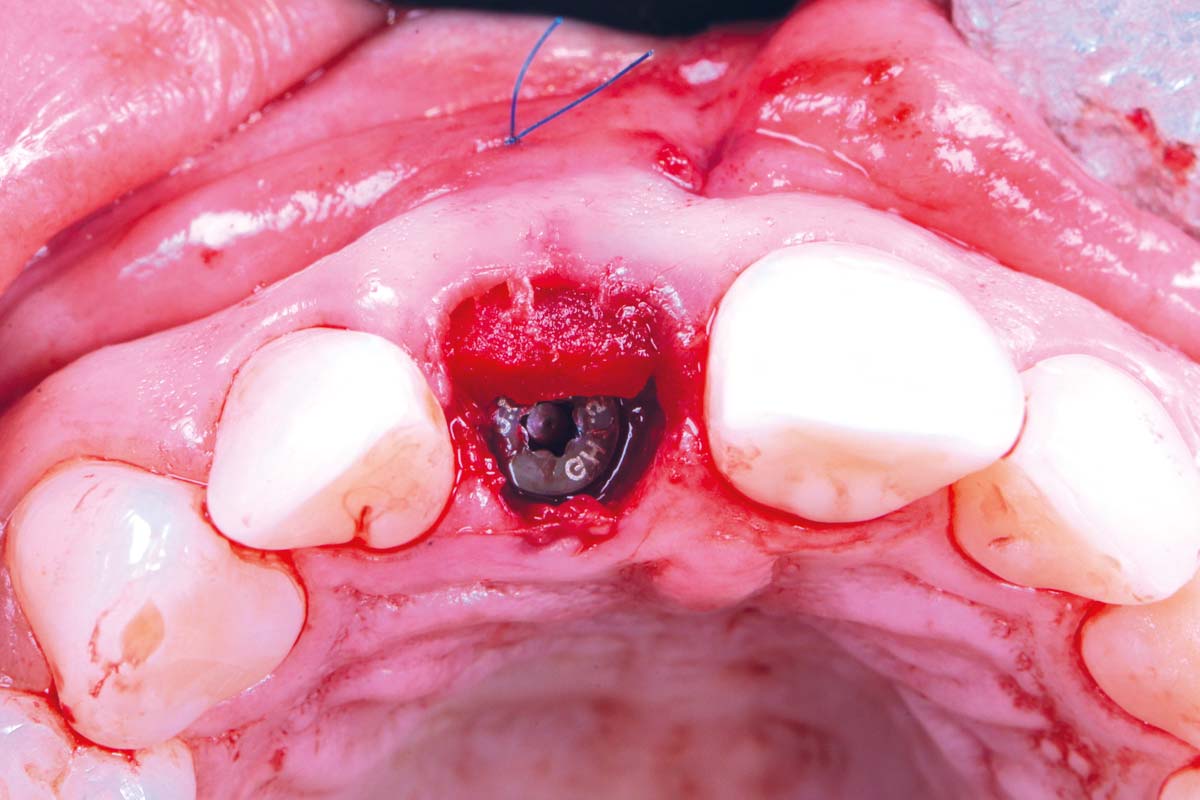

Initial clinical situation - Central incisors with dental destruction and periapical pathology